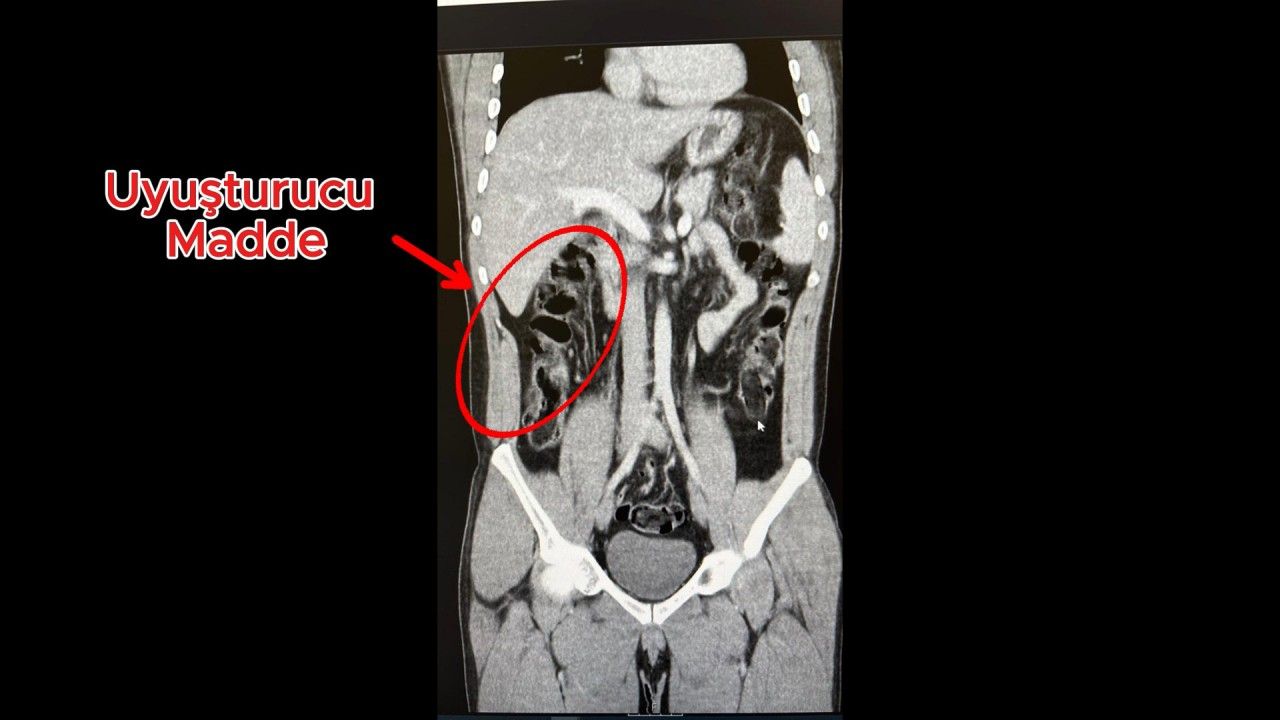

İl Emniyet Müdürlüğü Narkotik Suçlarla Mücadele Şube Müdürlüğü ekipleri, S.S. ve F.M.K. adlı şüphelilerin İran'dan Van'a geçtiğini, yanlarındaki uyuşturucuyu yutarak Antalya'ya geleceğini tespit etti. Şüphelilerin, uyuşturucuyu 'torbacı' olarak tabir edilen uyuşturucu satıcıları aracılığıyla piyasaya sürecekleri bilgisi üzerine ekipler, Antalya Havalimanında S.S. ve F.M.K.'yi yakalayıp gözaltına aldı. Aramalarda üzerlerinde uyuşturucuya rastlanmayan 2 şüpheli, iç muayene için hastaneye götürüldü. Hastanedeki iç beden muayenesinde, 2 şüphelinin, toplam 278 gram 35 kapsül halinde eroini yuttuğu saptandı. 'Uyuşturucu veya uyarıcı madde ticareti yapmak ve sağlamak' suçundan tutuklanan 2 şüphelinin havalimanındaki görüntüleri, muayene edilme anları ve yuttukları kapsüllerin yer aldığı film sonuçları kameralara yansıdı. (DHA)